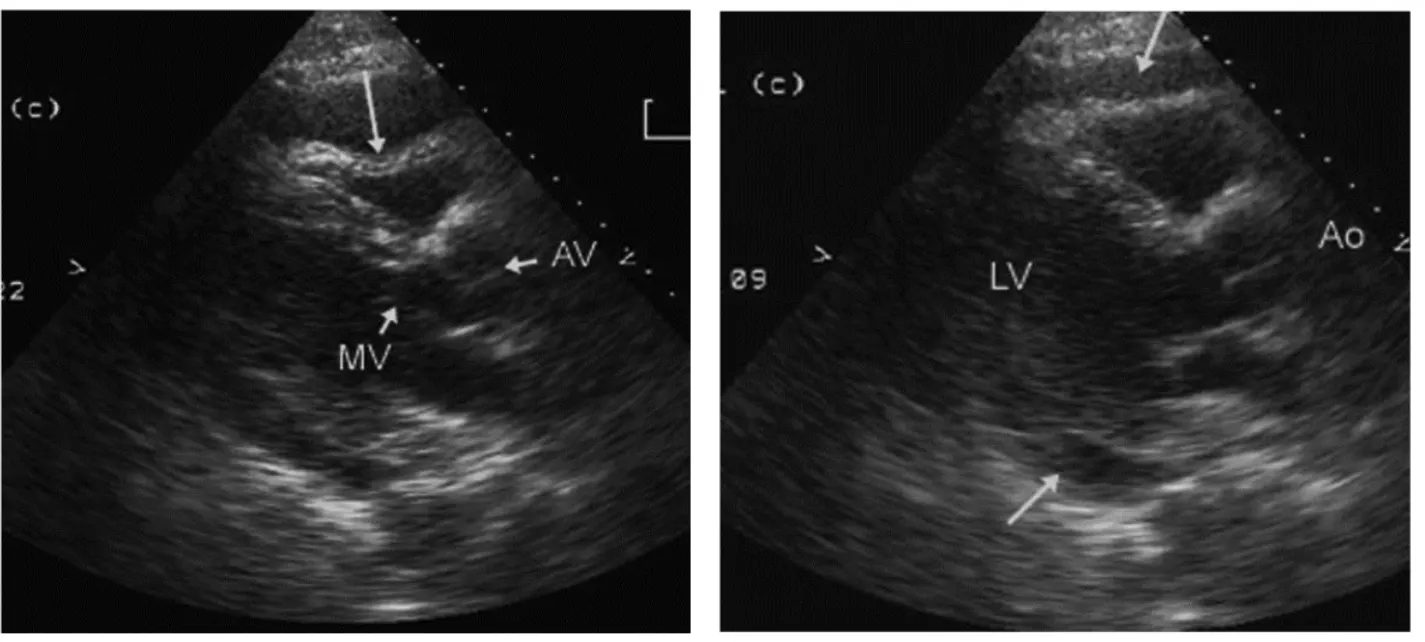

Subcostal technique

>익숙하고, 만약 응급상황에서 blind 로 해야된다면 가장 선호됨

단점으로는 liver 찌를 위험이 있고 찌르는 깊이가 깊음. 비만환자에서는 어렵

Subxiphoid 에서 insertion 하여 왼쪽 어깨쪽을 향해 넣음

Cartilage cage를 지나면 니들 앵글을 30도로 낮춘다

간 찌르지 않도록 조심

Parasternal technique

가장 가까운 위치이나 proximal LAD puncutre의 위험이 있고, internal mammary artery/intercostal vessel injury의 위험성이 있음

5,6번째 갈비뼈 위 경계선이자, Sternum margin 바로 옆에 needle insertion

•

피부에 직각으로 들어가야 함

Sternum margin에서 1cm 이상 옆으로 가게 되면 internal mammaryh vessel injury의 위험

Apical technique

얕기 때문에 선호되는 방법.

LV 가 두껍기때문에 혹시라도 myocardium puncture 해도 Cx 가능성이 다른데에 비해 낮음

5,6,7번째 ICS에서

Parasternal approach 에서 최소 5센치 옆

Rib 윗쪽 경계선을 타고 니들 전진